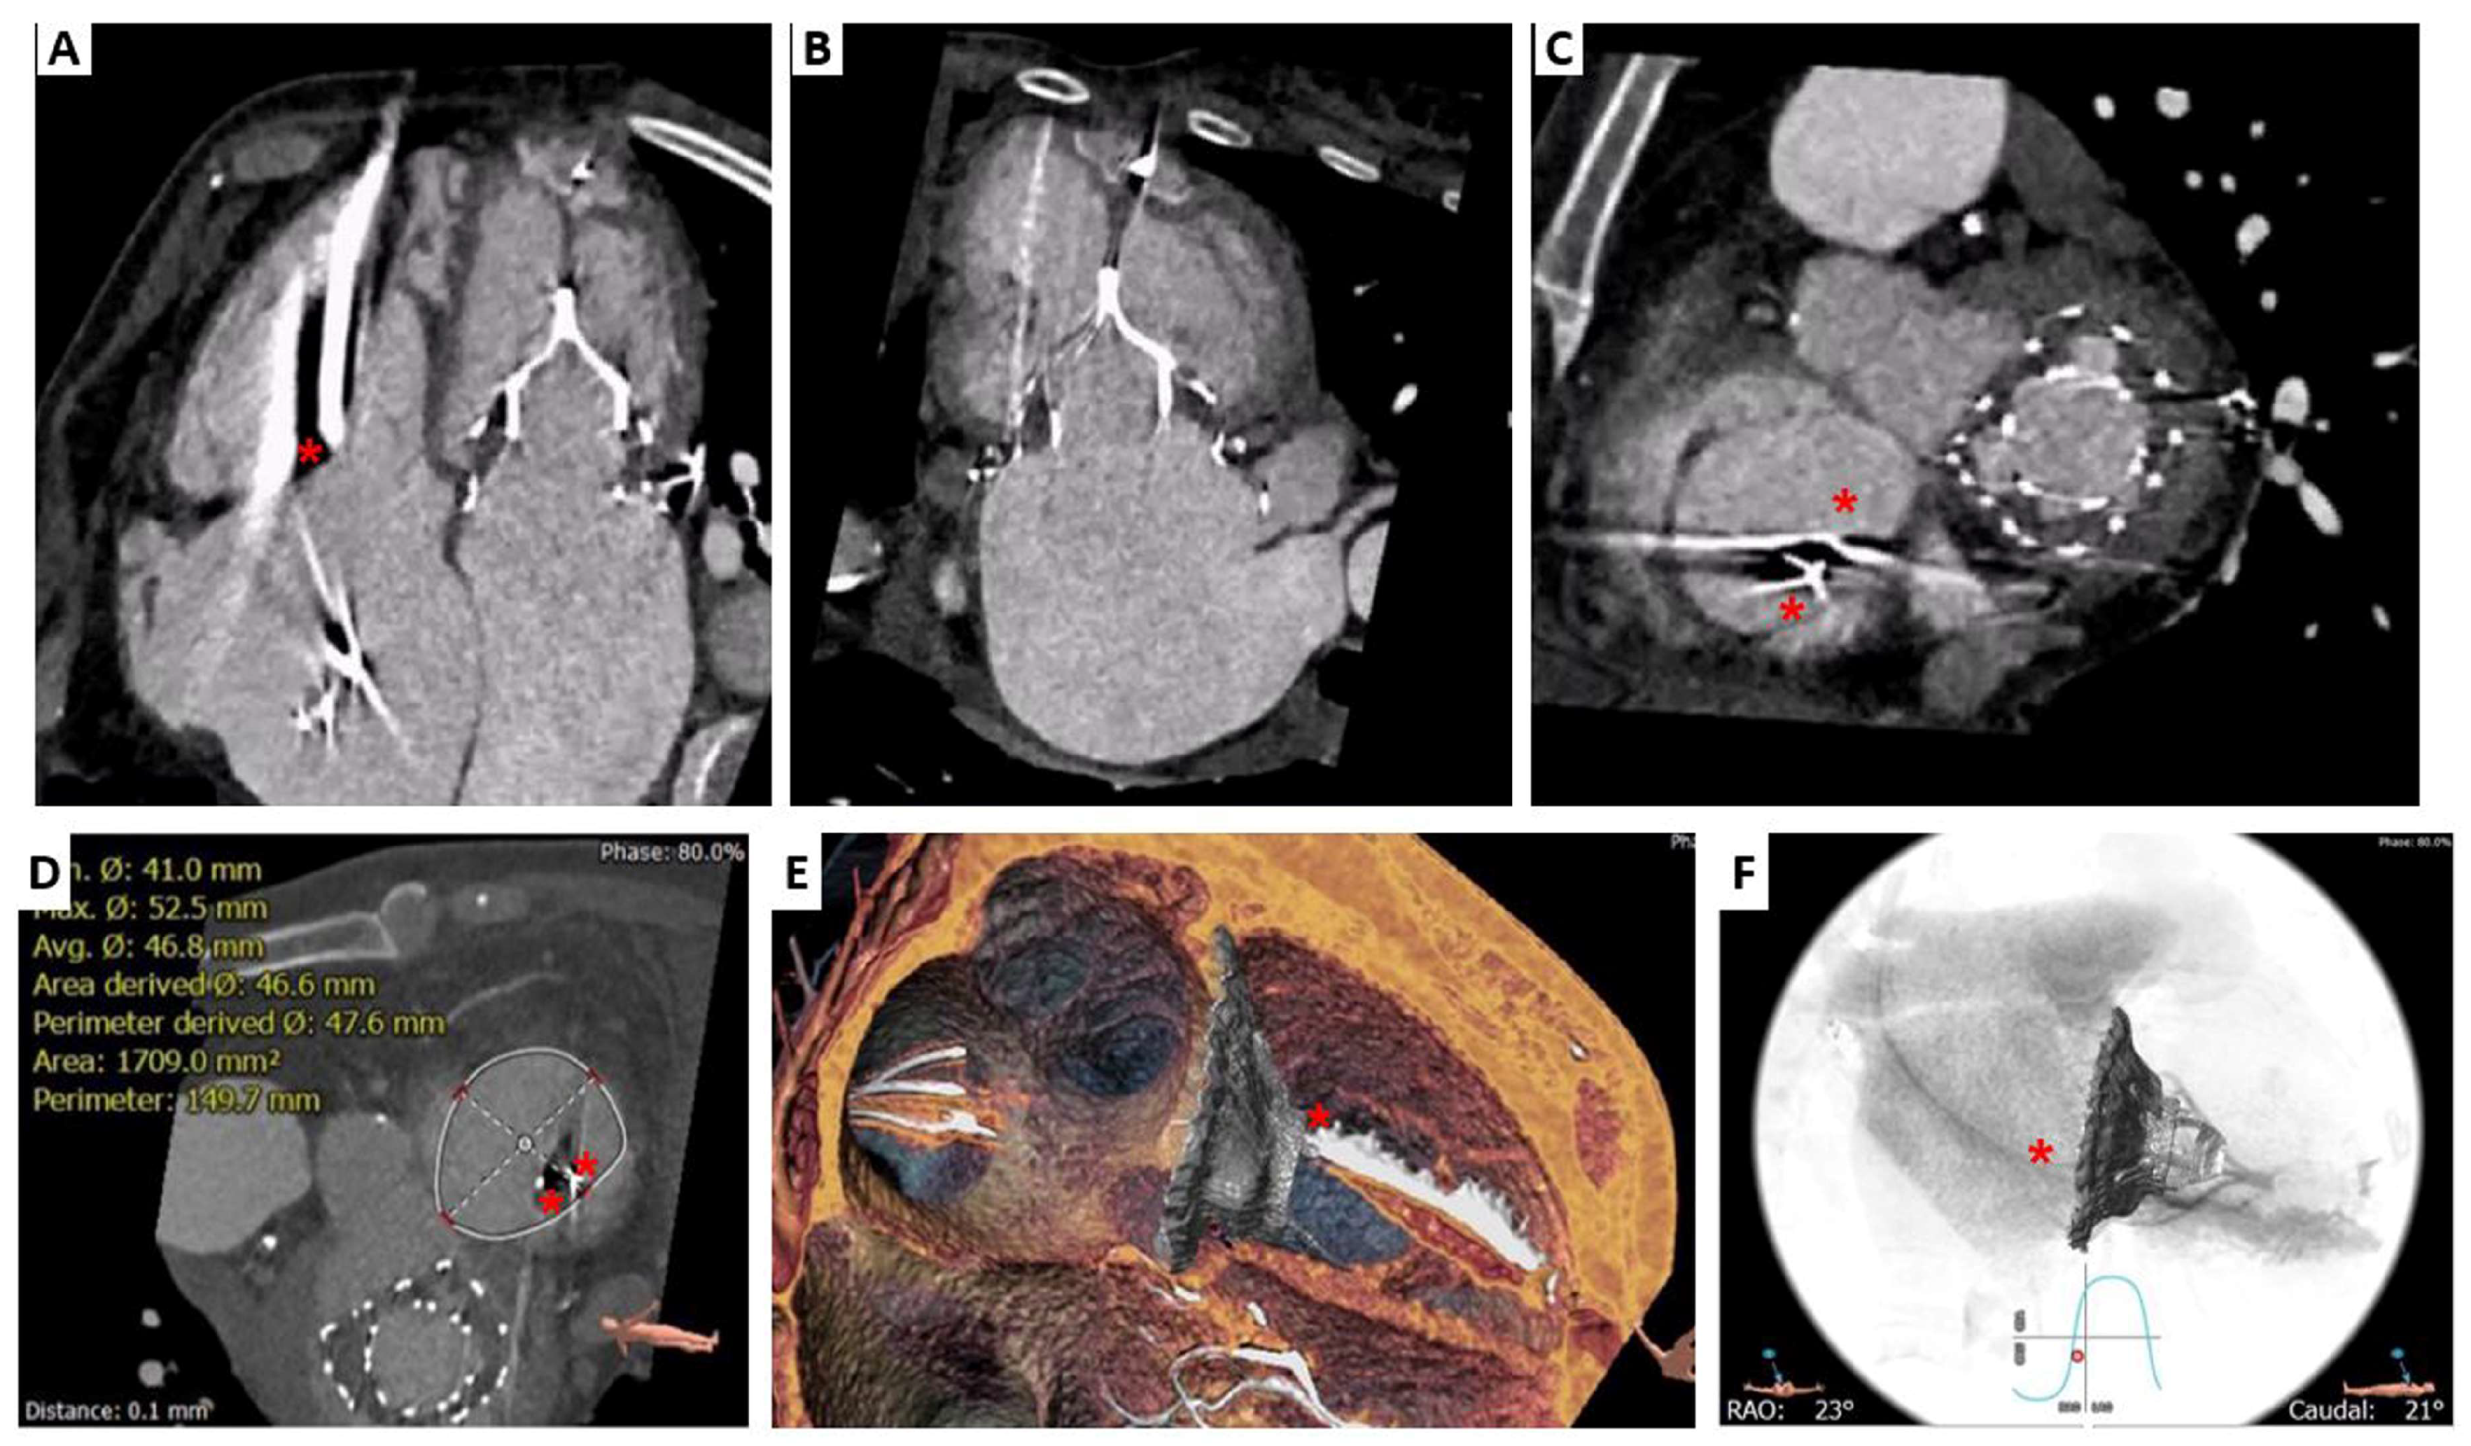

2. Cardiovalve Cases

4.2. Cardiovalve

- Barreiro-Perez, M.; Estevez-Loureiro, R.; Baz, J.A.; Piñón, M.A.; Maisano, F.; Puga, L.; Caneiro-Queija, B.; Iñiguez-Romo, A. Cardiovalve Transfemoral Tricuspid Valve Replacement Assisted With CT-Fluoroscopy Fusion Imaging. JACC Cardiovasc. Interv. 2022, 15, e197–e199. [Google Scholar] [CrossRef]